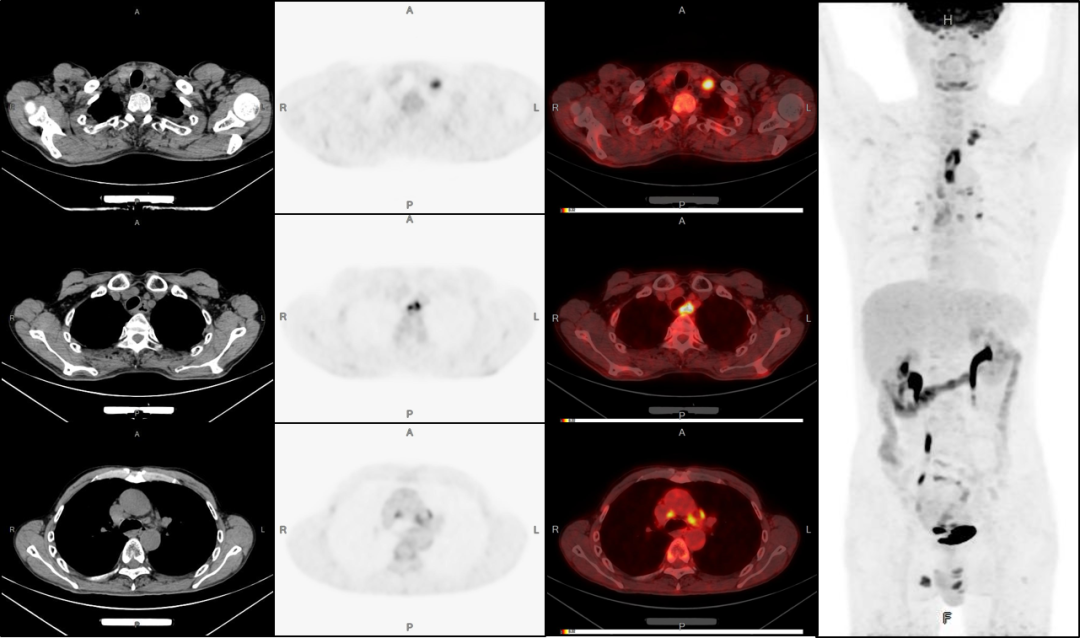

病例2:男性,51歲,復咳嗽無痰半年余;發現左側鎖骨內腫塊數月

PET/CT檢查:

1、食管上段癌伴左側鎖骨區淋巴結轉移可能;

2、縱膈及兩側肺門多發淋巴結轉移

3、雙股骨上段轉移可能。